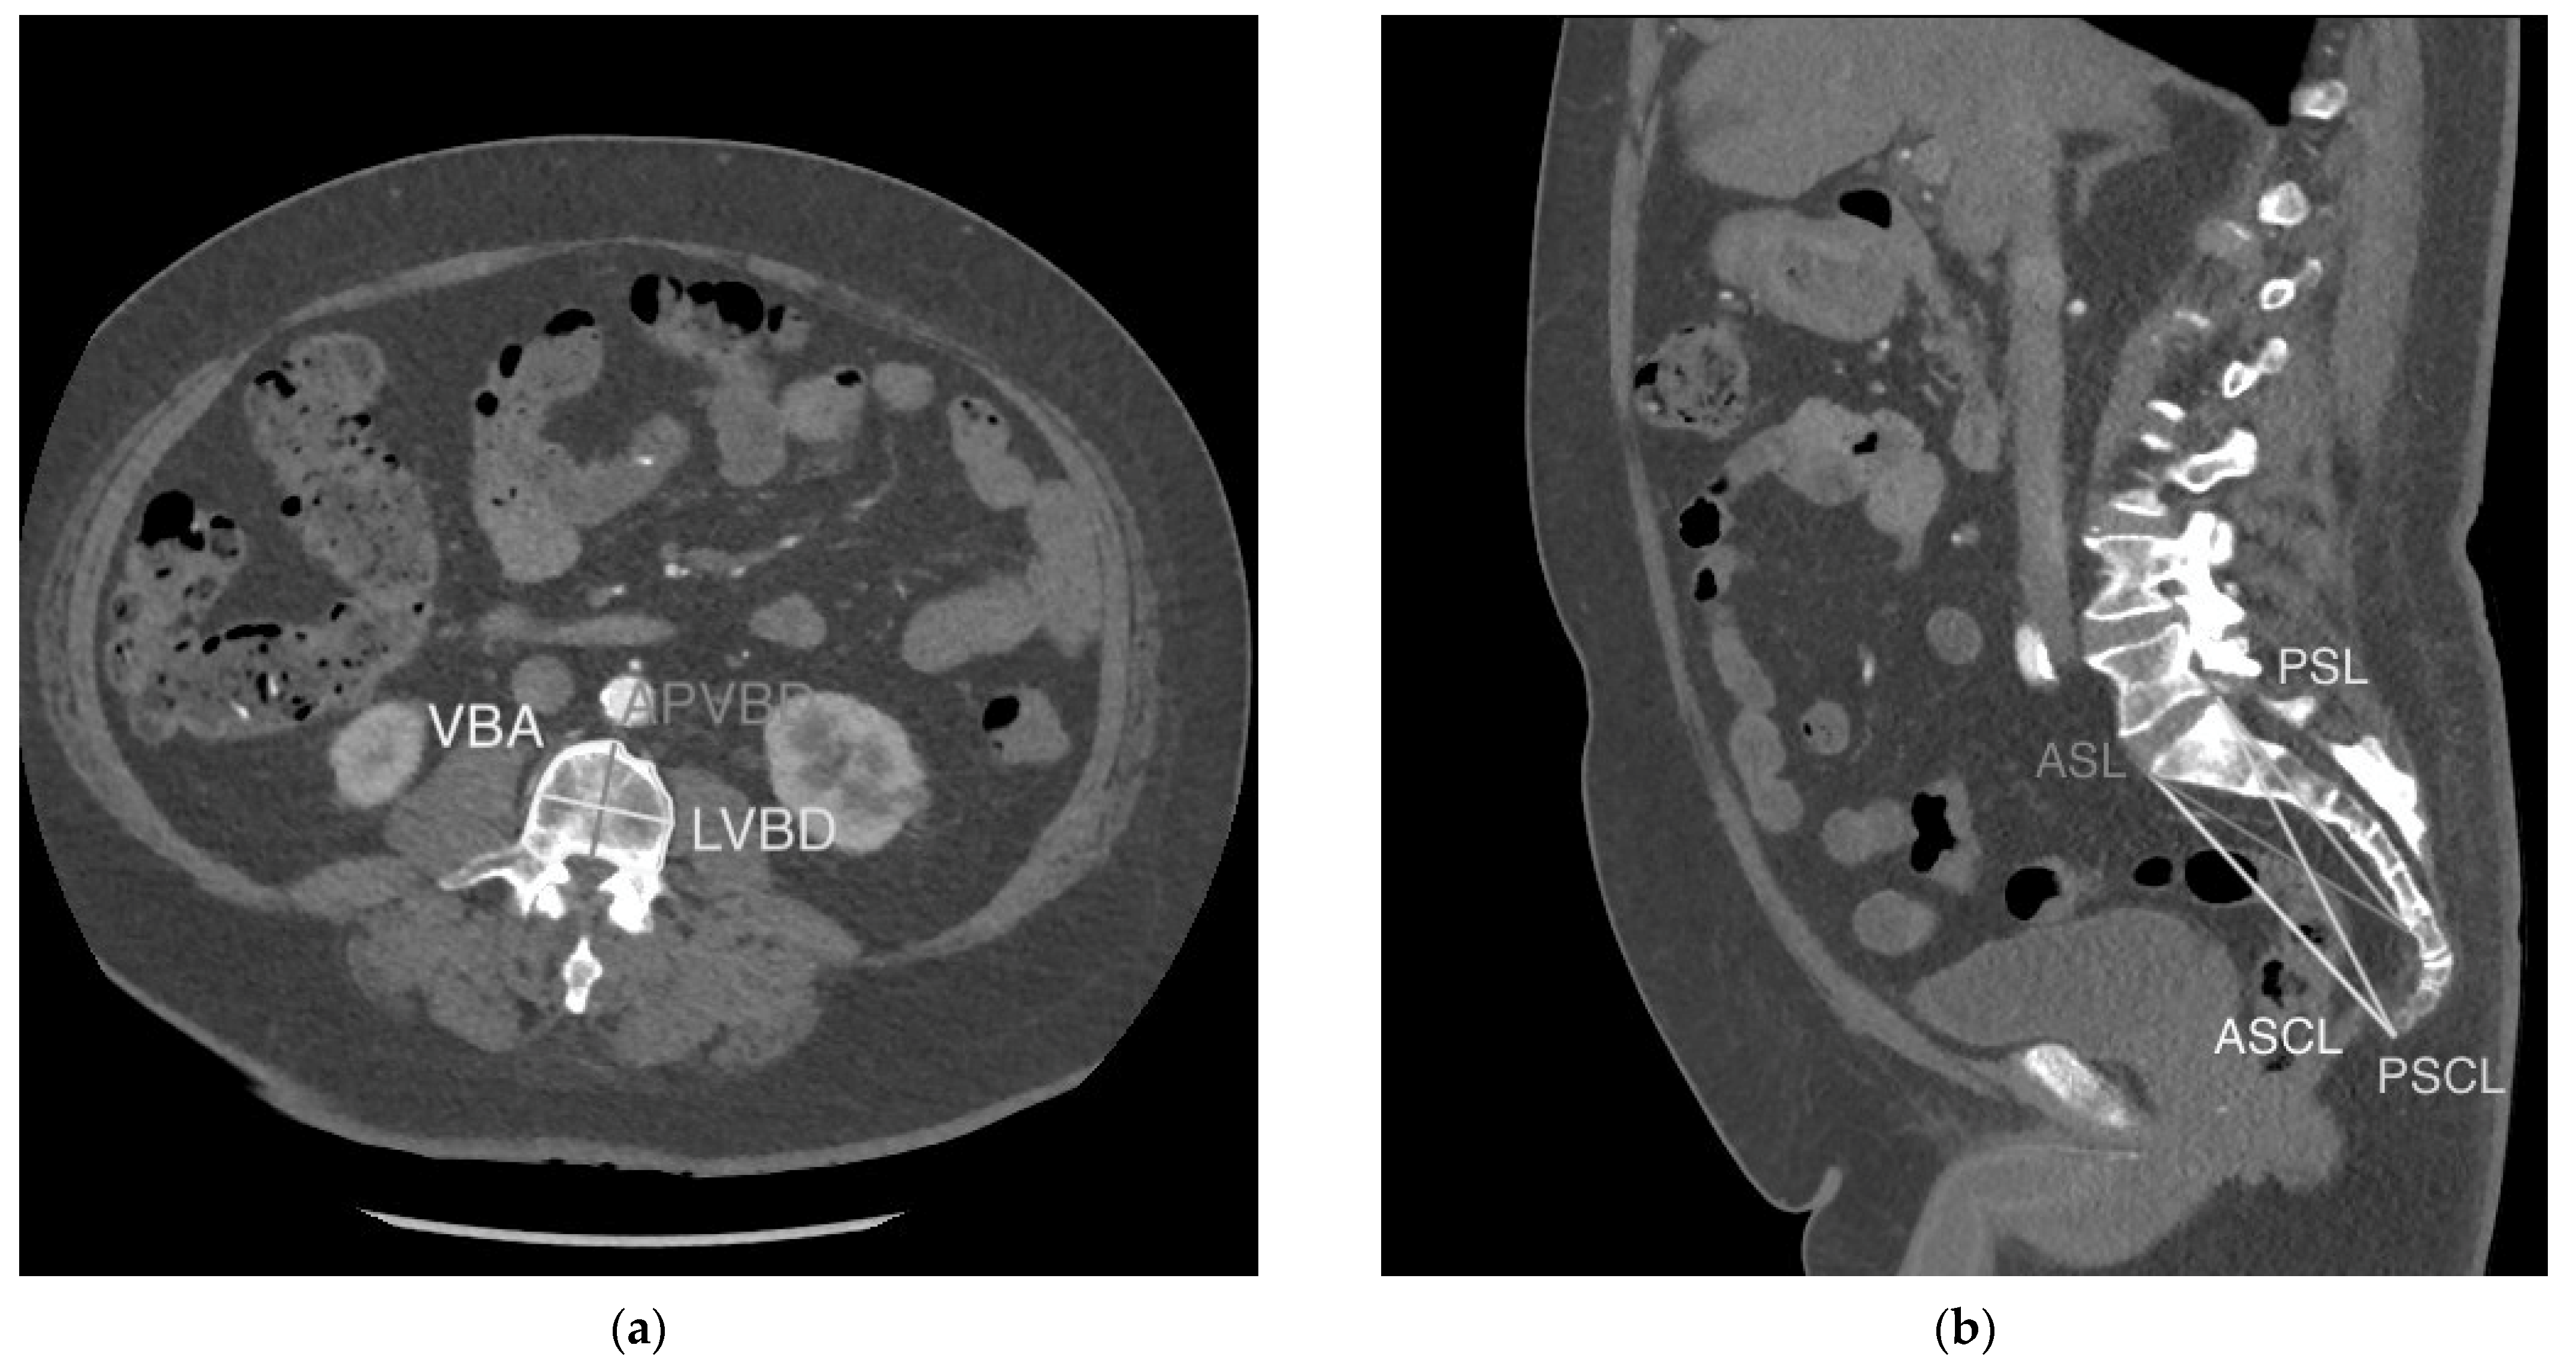

| VBA | Cross-sectional area of the vertebral body just inferior to the superior endplate |

| LVBD | Maximum linear distance between two points on the outer cortex of the vertebral body in the lateral (coronal) dimension on axial imaging just inferior to the superior endplate |

| APVBD | Maximum linear distance between two points on the outer cortex of the vertebral body in the antero-posterior (sagittal) dimension on axial imaging just inferior to the superior endplate |

| ASL | Linear distance between the most anterosuperior point of the first sacral vertebra (S1) and the most anteroinferior point of the fifth sacral vertebra (S5) |

| PSL | Linear distance between the most posterosuperior point of S1 and the most anteroinferior point of the S5 vertebral body |

| ASCL | Linear distance between the most anterosuperior point of S1 and the most anteroinferior point of the last coccygeal vertebral body |

| PSCL | Linear distance between the most posterosuperior point of S1 and the most anteroinferior point of the last coccygeal vertebral body |